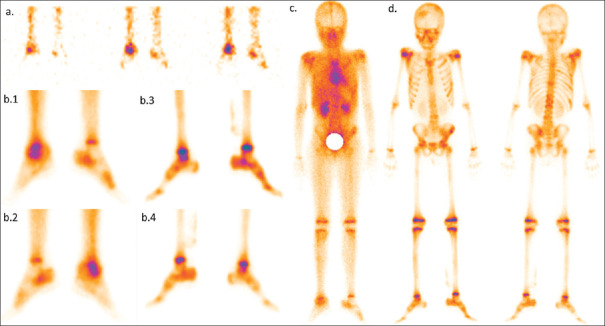

Bambina di 7 anni con dolore e gonfiore alla caviglia destra; indici di flogosi (VES e PCR) elevati, ma radiografia iniziale negativa. La paziente è stata sottoposta a scintigrafia ossea trifasica con 99mTc-MDP.

La fase di flusso della caviglia (a) ha mostrato una vascolarizzazione aumentata a destra. Le immagini statiche di blood-pool (b. 1 e b. 2) hanno evidenziato un aumentato accumulo del tracciante nell’articolazione della caviglia destra, mentre le immagini statiche tardive (b. 3 e b. 4) hanno mostrato un lieve aumento della captazione nell’articolazione tibio-tarsica destra con captazione ossea relativamente normale, quadro suggestivo di cellulite. L’immagine whole-body di blood-pool (c) ha mostrato un lieve aumento dell’accumulo ematico nel cranio (frontale destro e parietale sn), in entrambe le spalle e in alcune coste di destra, oltre al coinvolgimento della caviglia. Le stesse regioni hanno mostrato un’aumentata captazione nelle immagini whole-body tardive (d) acquisite dopo 3 ore. È stata posta diagnosi di osteomielite multifocale. L’aspirazione del liquido articolare dalla caviglia destra ha rivelato la presenza di bacilli tubercolari.